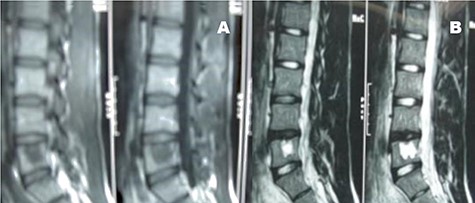

A 26-year-old male presented with pain over the lower lumbar area. Physical examination and laboratory tests were unremarkable with no neurologic deficit. X-ray and CT scans showed a lytic lesion with a sclerotic border in the right half of the body of the L5 vertebra (Figs 6 and 7). MRI showed a well-defined low signal lesion in T1 weighted images and high signal lesion in T2 weighted images (Fig. 8). The bone scan was negative. The patient underwent surgery and the lesion was extracted through the right pedicle and the remaining cavity was filled with an autologous bone graft from the iliac crest and right-side posterior fusion was done from L4 to L5 (Fig. 9). The pathology report was consistent with SBC. The patient had no recurrence seven years after surgery.

Case 2, Sagittal T2-weighted and T1-weighted MR images of lumbar vertebrae show the body and homogeneous cystic lesion of L5.